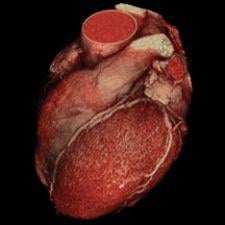

One of the clinical applications that comes with the software is VOXAR 3D CARDIAMETRIX for analysis of CT cardiac images. CARDIAMETRIX provides reading capability for cardiac 4-D analysis, coronary vessel analysis, left ventricular analysis and calcium scoring.

VOXAR 3D ENTERPRISE accelerates the speed at which image studies can be loaded, read and communicated. It also provides real-time interaction with VOXAR 3D’s visualization and analysis tools and clinical applications, VESSELMETRIX and CARDIAMETRIX.